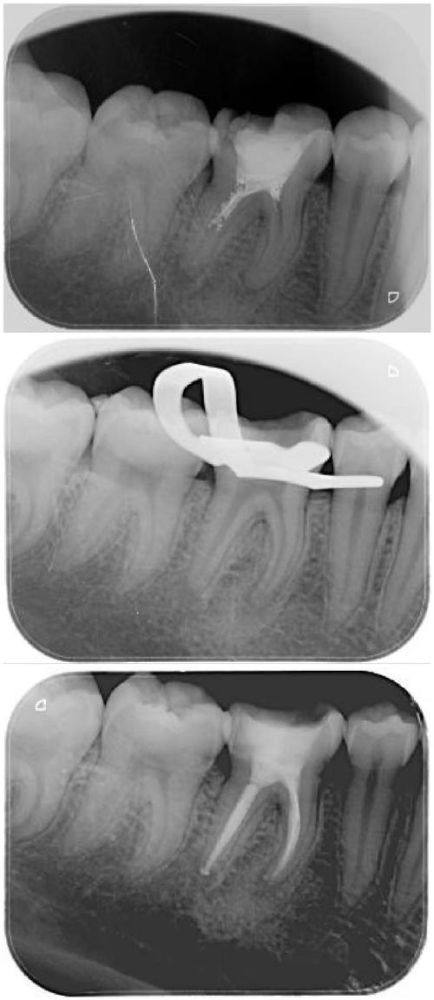

在探讨“牙齿根管治疗后一定要做牙套吗”之前,咱们先来了解下根管治疗。简单来说,根管治疗就像是给牙齿做一次深度清洁和修复。医生会用专精的器材,把牙齿根管里的感染物质清理干净,然后进行填塞,以此来控制牙齿内部的感染。做根管治疗可得乖乖听医生的话,按照要求来,这样才能确保治疗成效。不过呢,根管治疗之后,牙齿会发生一些变化,其中一个就是牙齿的脆性会有所提高。这就好比原本坚固的东西,变得没那么“禁造”了。

这“牙齿根管治疗后一定要做牙套吗”还真没个准话,得看牙齿的具体状况。如果你自己拿不准,更好的办法就是去问医生。医生会通过专精的检查,比如拍牙片等,来了解牙齿的情况,然后给出专精的建议。一般来说,如果牙齿缺损比较大、剩余牙体组织比较少,那做牙套的必要性就比较大;要是牙齿只是小问题,本身比较完整、坚硬,那可能不做牙套也行。所以,别自己瞎琢磨,做完根管治疗后,听医生的安排就好。